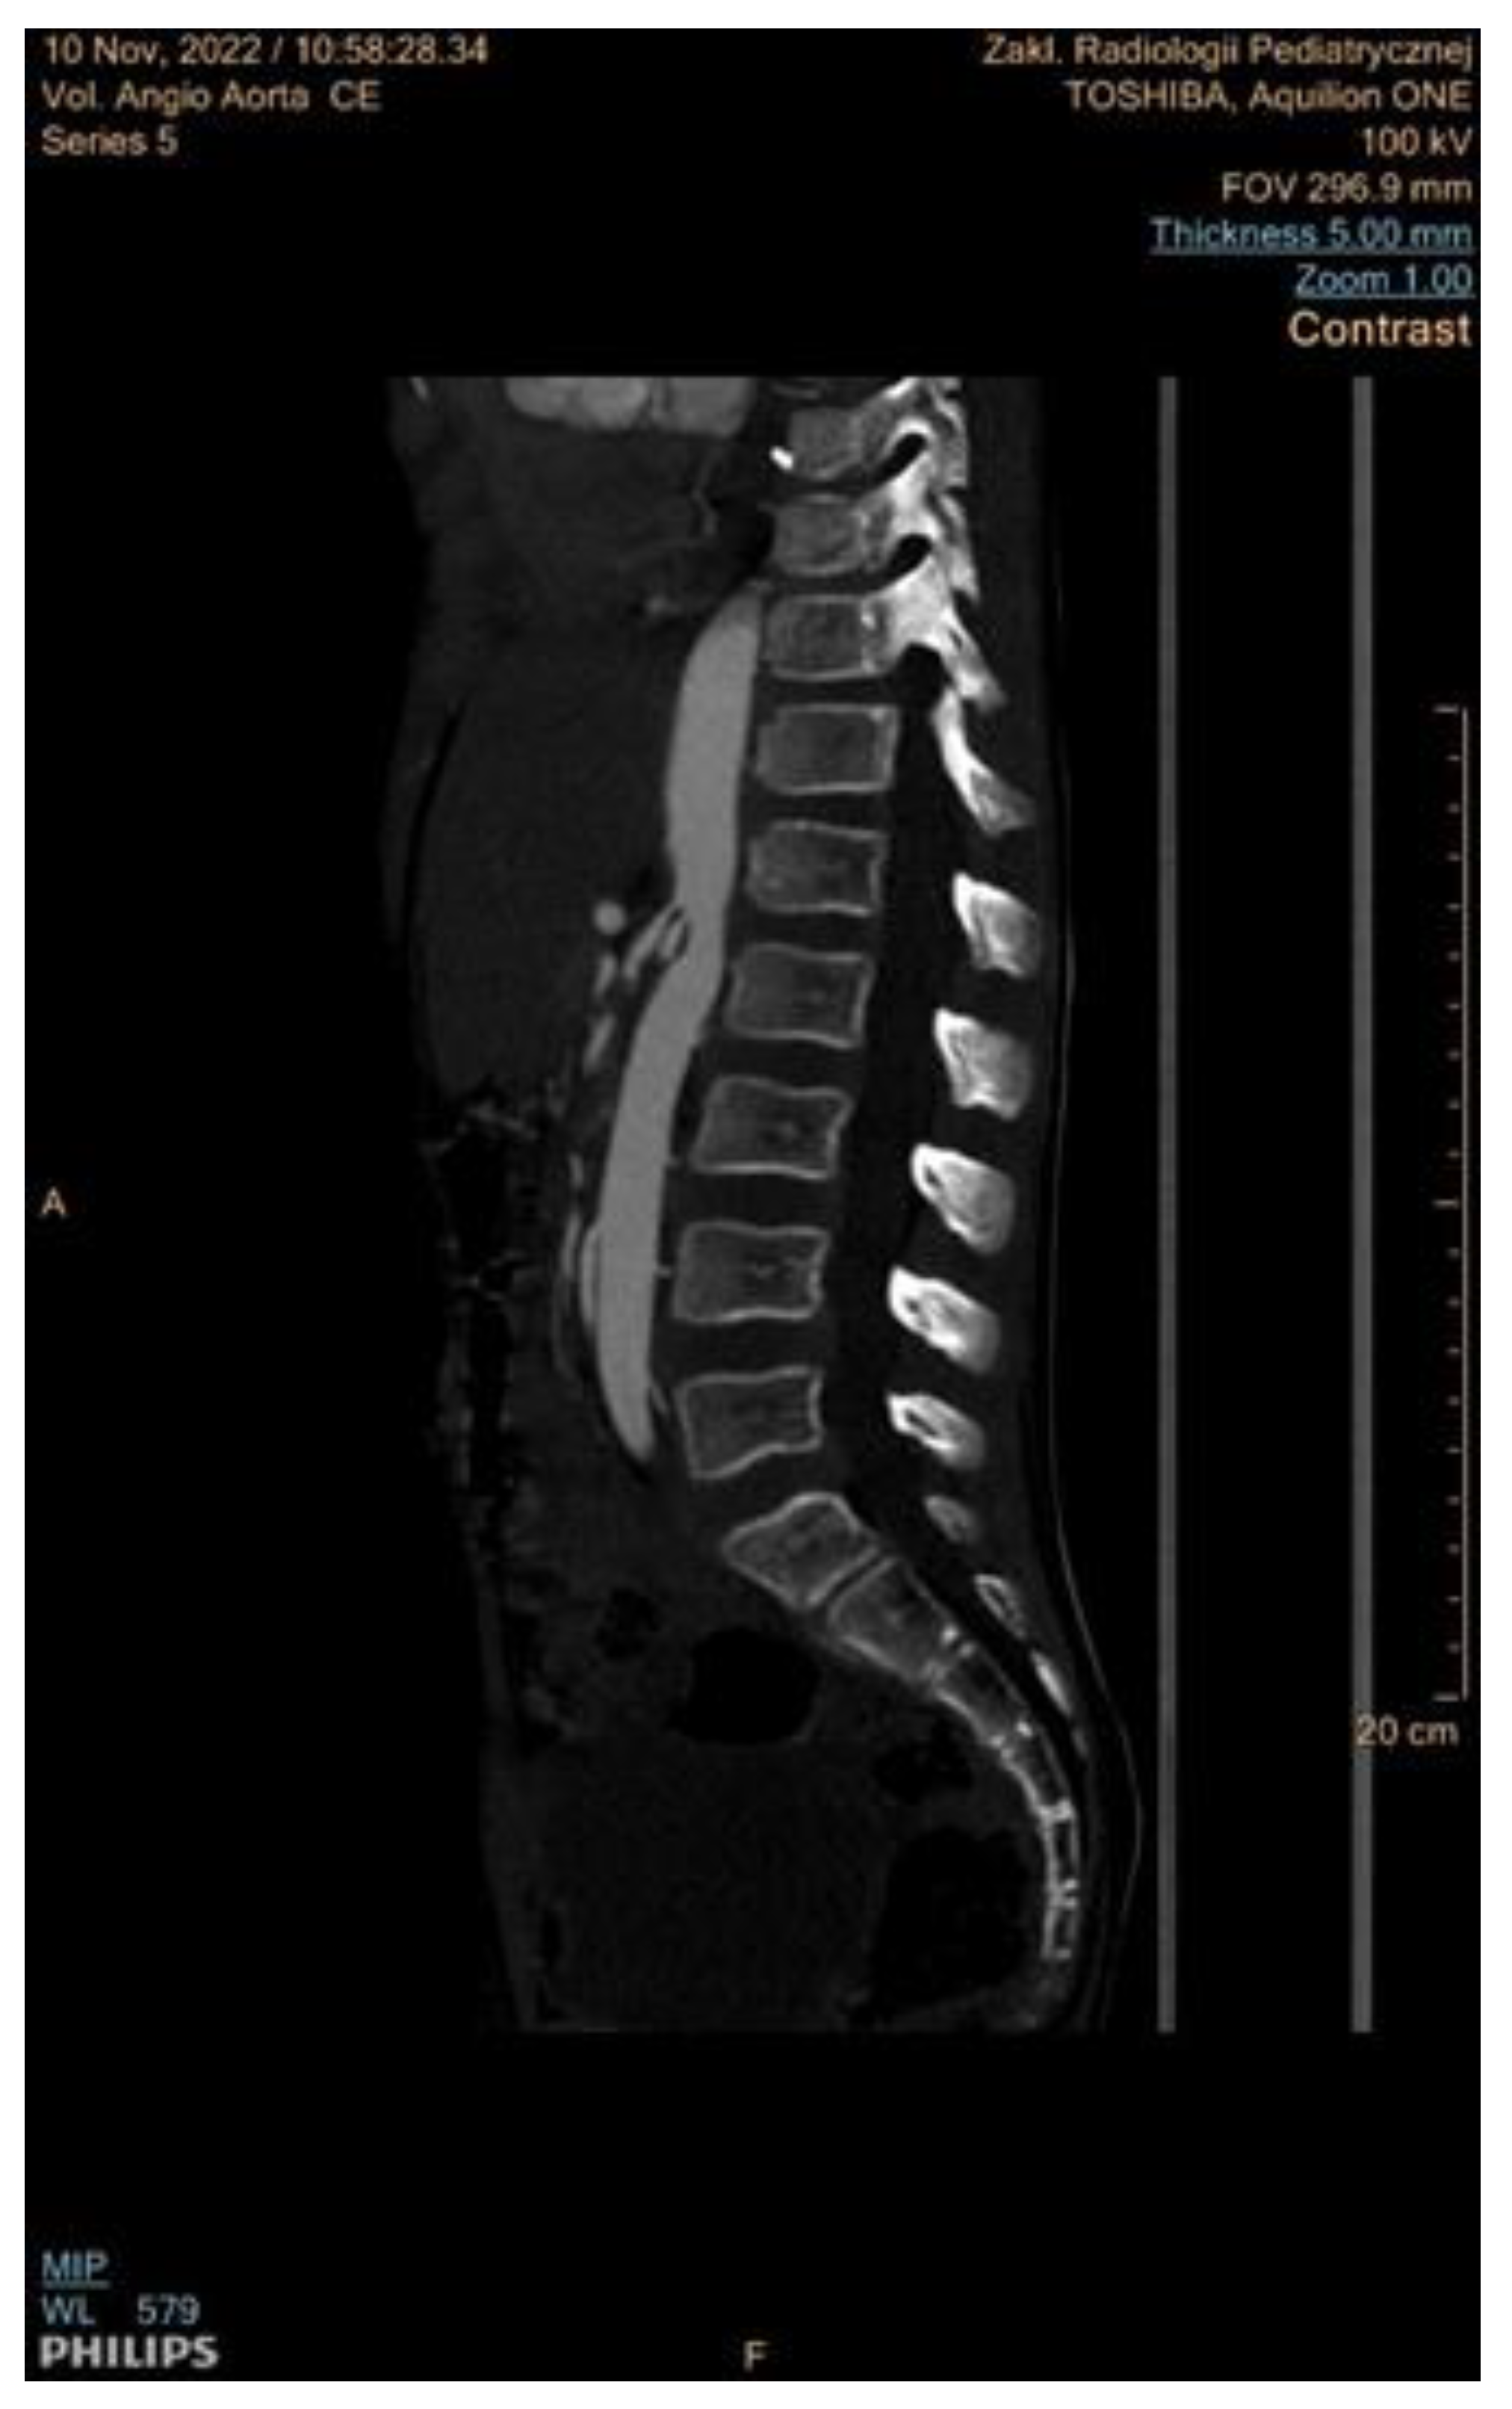

6.2. Computed Tomographic Angiography (CTA)

- Cai, Z.; Bai, E.-W.; Wang, G. A Reduced Radiation Dose CTA. IFAC Proc. Vol. 2012, 45, 184–189. [Google Scholar] [CrossRef]

- Roebuck, D.J. Childhood hypertension: What does the radiologist contribute? Pediatr. Radiol. 2008, 38, 501–507. [Google Scholar] [CrossRef] [PubMed]